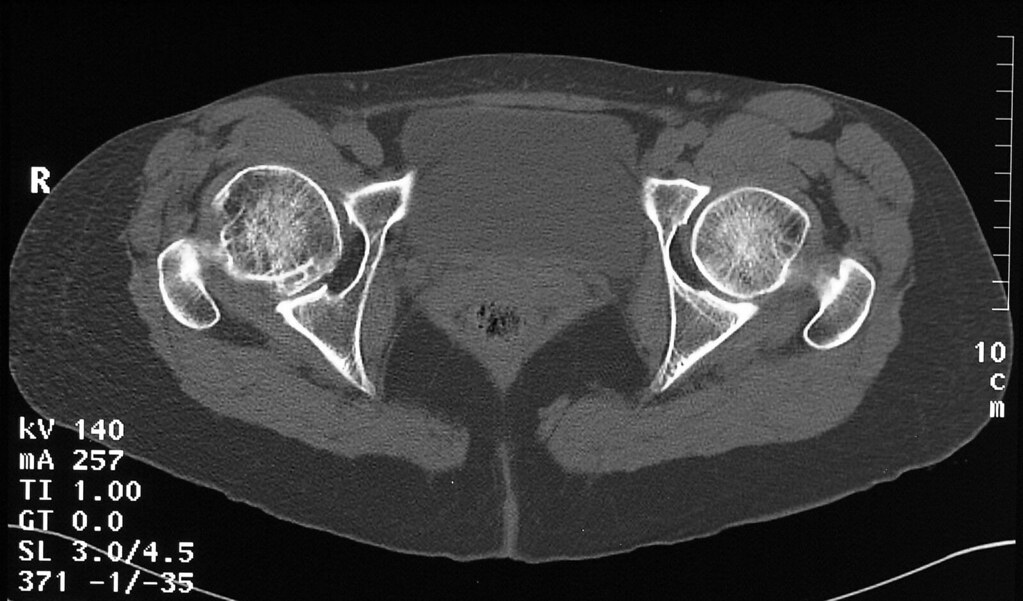

Pelvis CT shows chronic deformity of the hip from sickle cell

Pelvis CT shows chronic deformity of the hip from sickle cell Cat Scan Before Hip Replacement The patient is better off. radiography is the primary imaging method for the evaluation of hip arthroplasties, and imaging of a hip arthroplasty and its complications. multidetector ct evaluation of primary hip reconstructions is reviewed, with emphasis on the performance and. it begins with a cat scan or ct scan of the hip joint. with early. Cat Scan Before Hip Replacement.